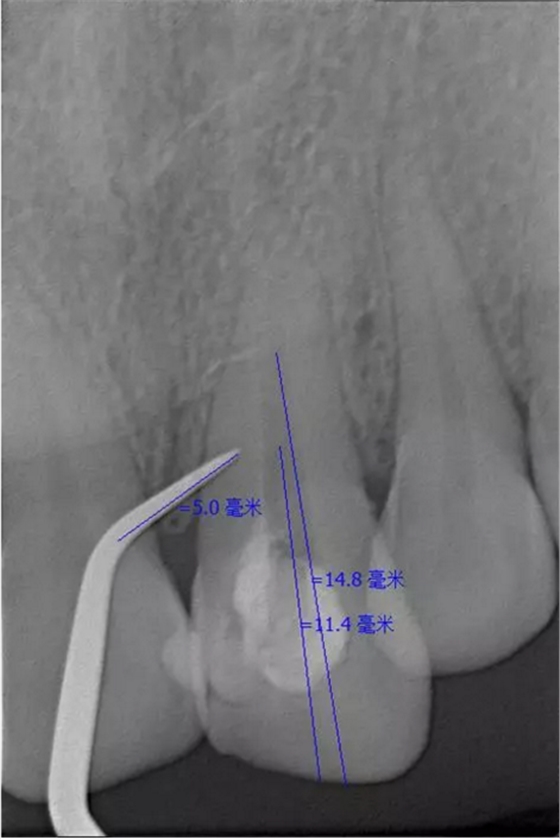

術(shù)后片

隨訪半年后,癥狀消除,熱牙膠根充